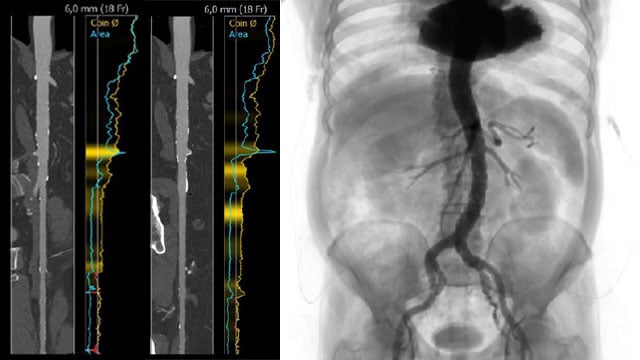

A challenging valve-in-valve scenario in a patient with prior aortic coarctation repair

A 79-year-old with a degenerated aortic bioprosthesis after complex coarctation surgery challenges conventional strategies. Which access route would you choose?